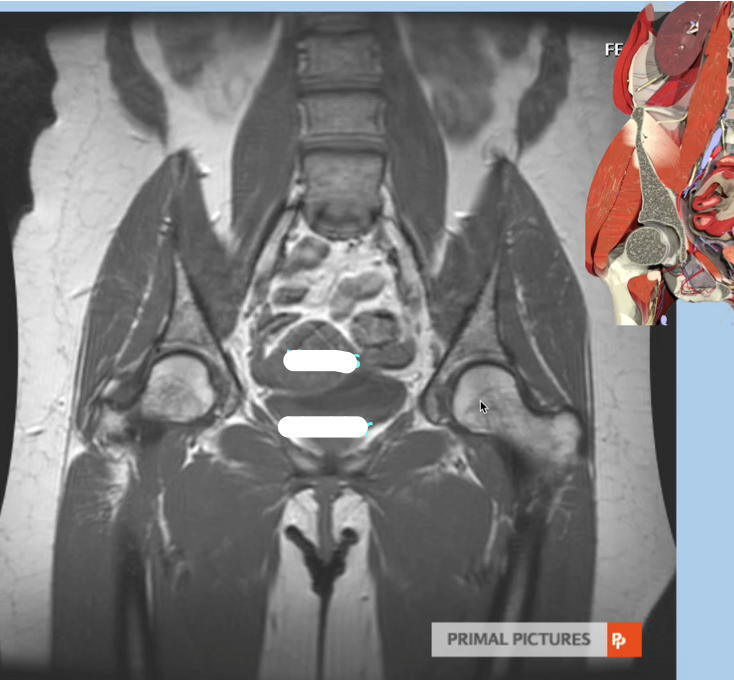

Imaging modality & complete the labels

Coronal MRI

A

Coronal MRI of male pelvis